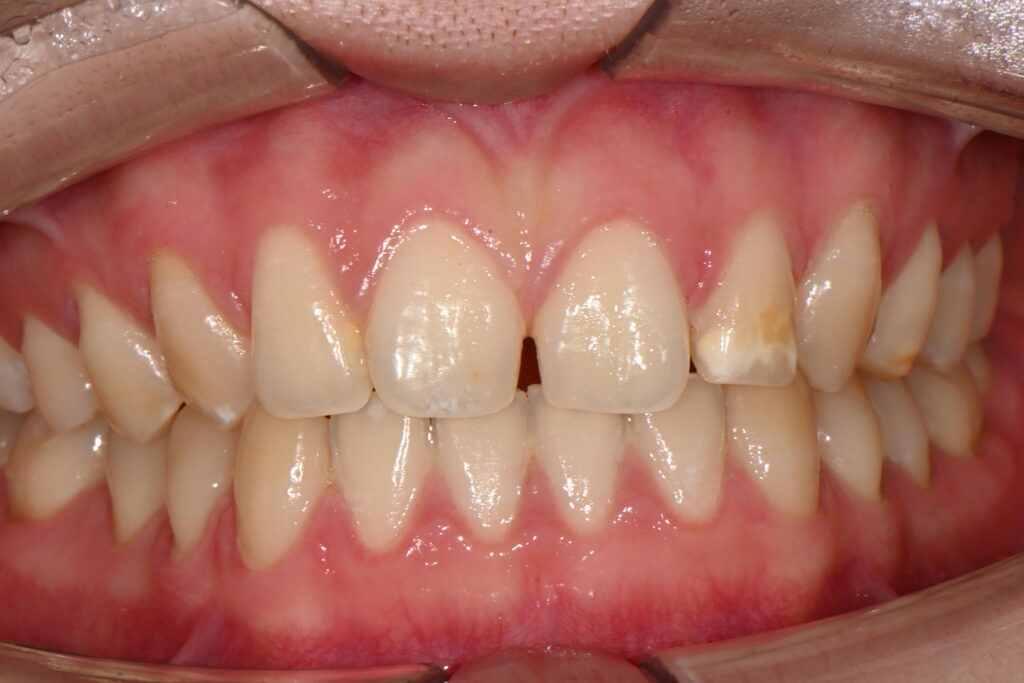

전체적인 앞니 미소가 힘들다고 내원하신경우입니다

이렇게 앞니가 벌어진 경우는 원인이 참 많습니다

이 케이스경우에는 치아형태의 이상입니다

일명 외소치와 쐐기모양 치아형태를 동시에 나타나고 있습니다

쐐기모양의 치아형태 모양을 띄면서 사이공간이 생긴 케이스입니다